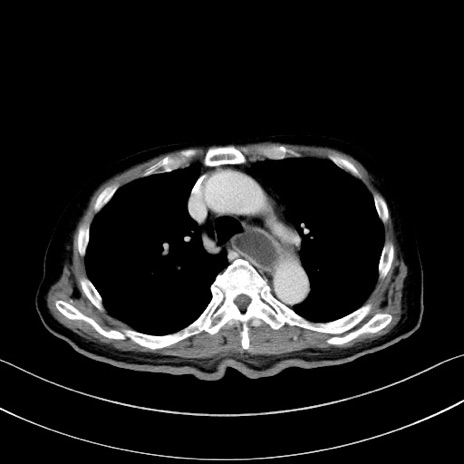

症例28(横断像)

【症例】60歳代男性

【主訴】嘔吐

【現病歴】胃癌にて胃全摘後。食思不振が悪化し、夜中に嘔吐することがある。

【既往歴】胃癌、胃全摘、脾摘、胆摘後

【データ】WBC 5900、CRP 10.56